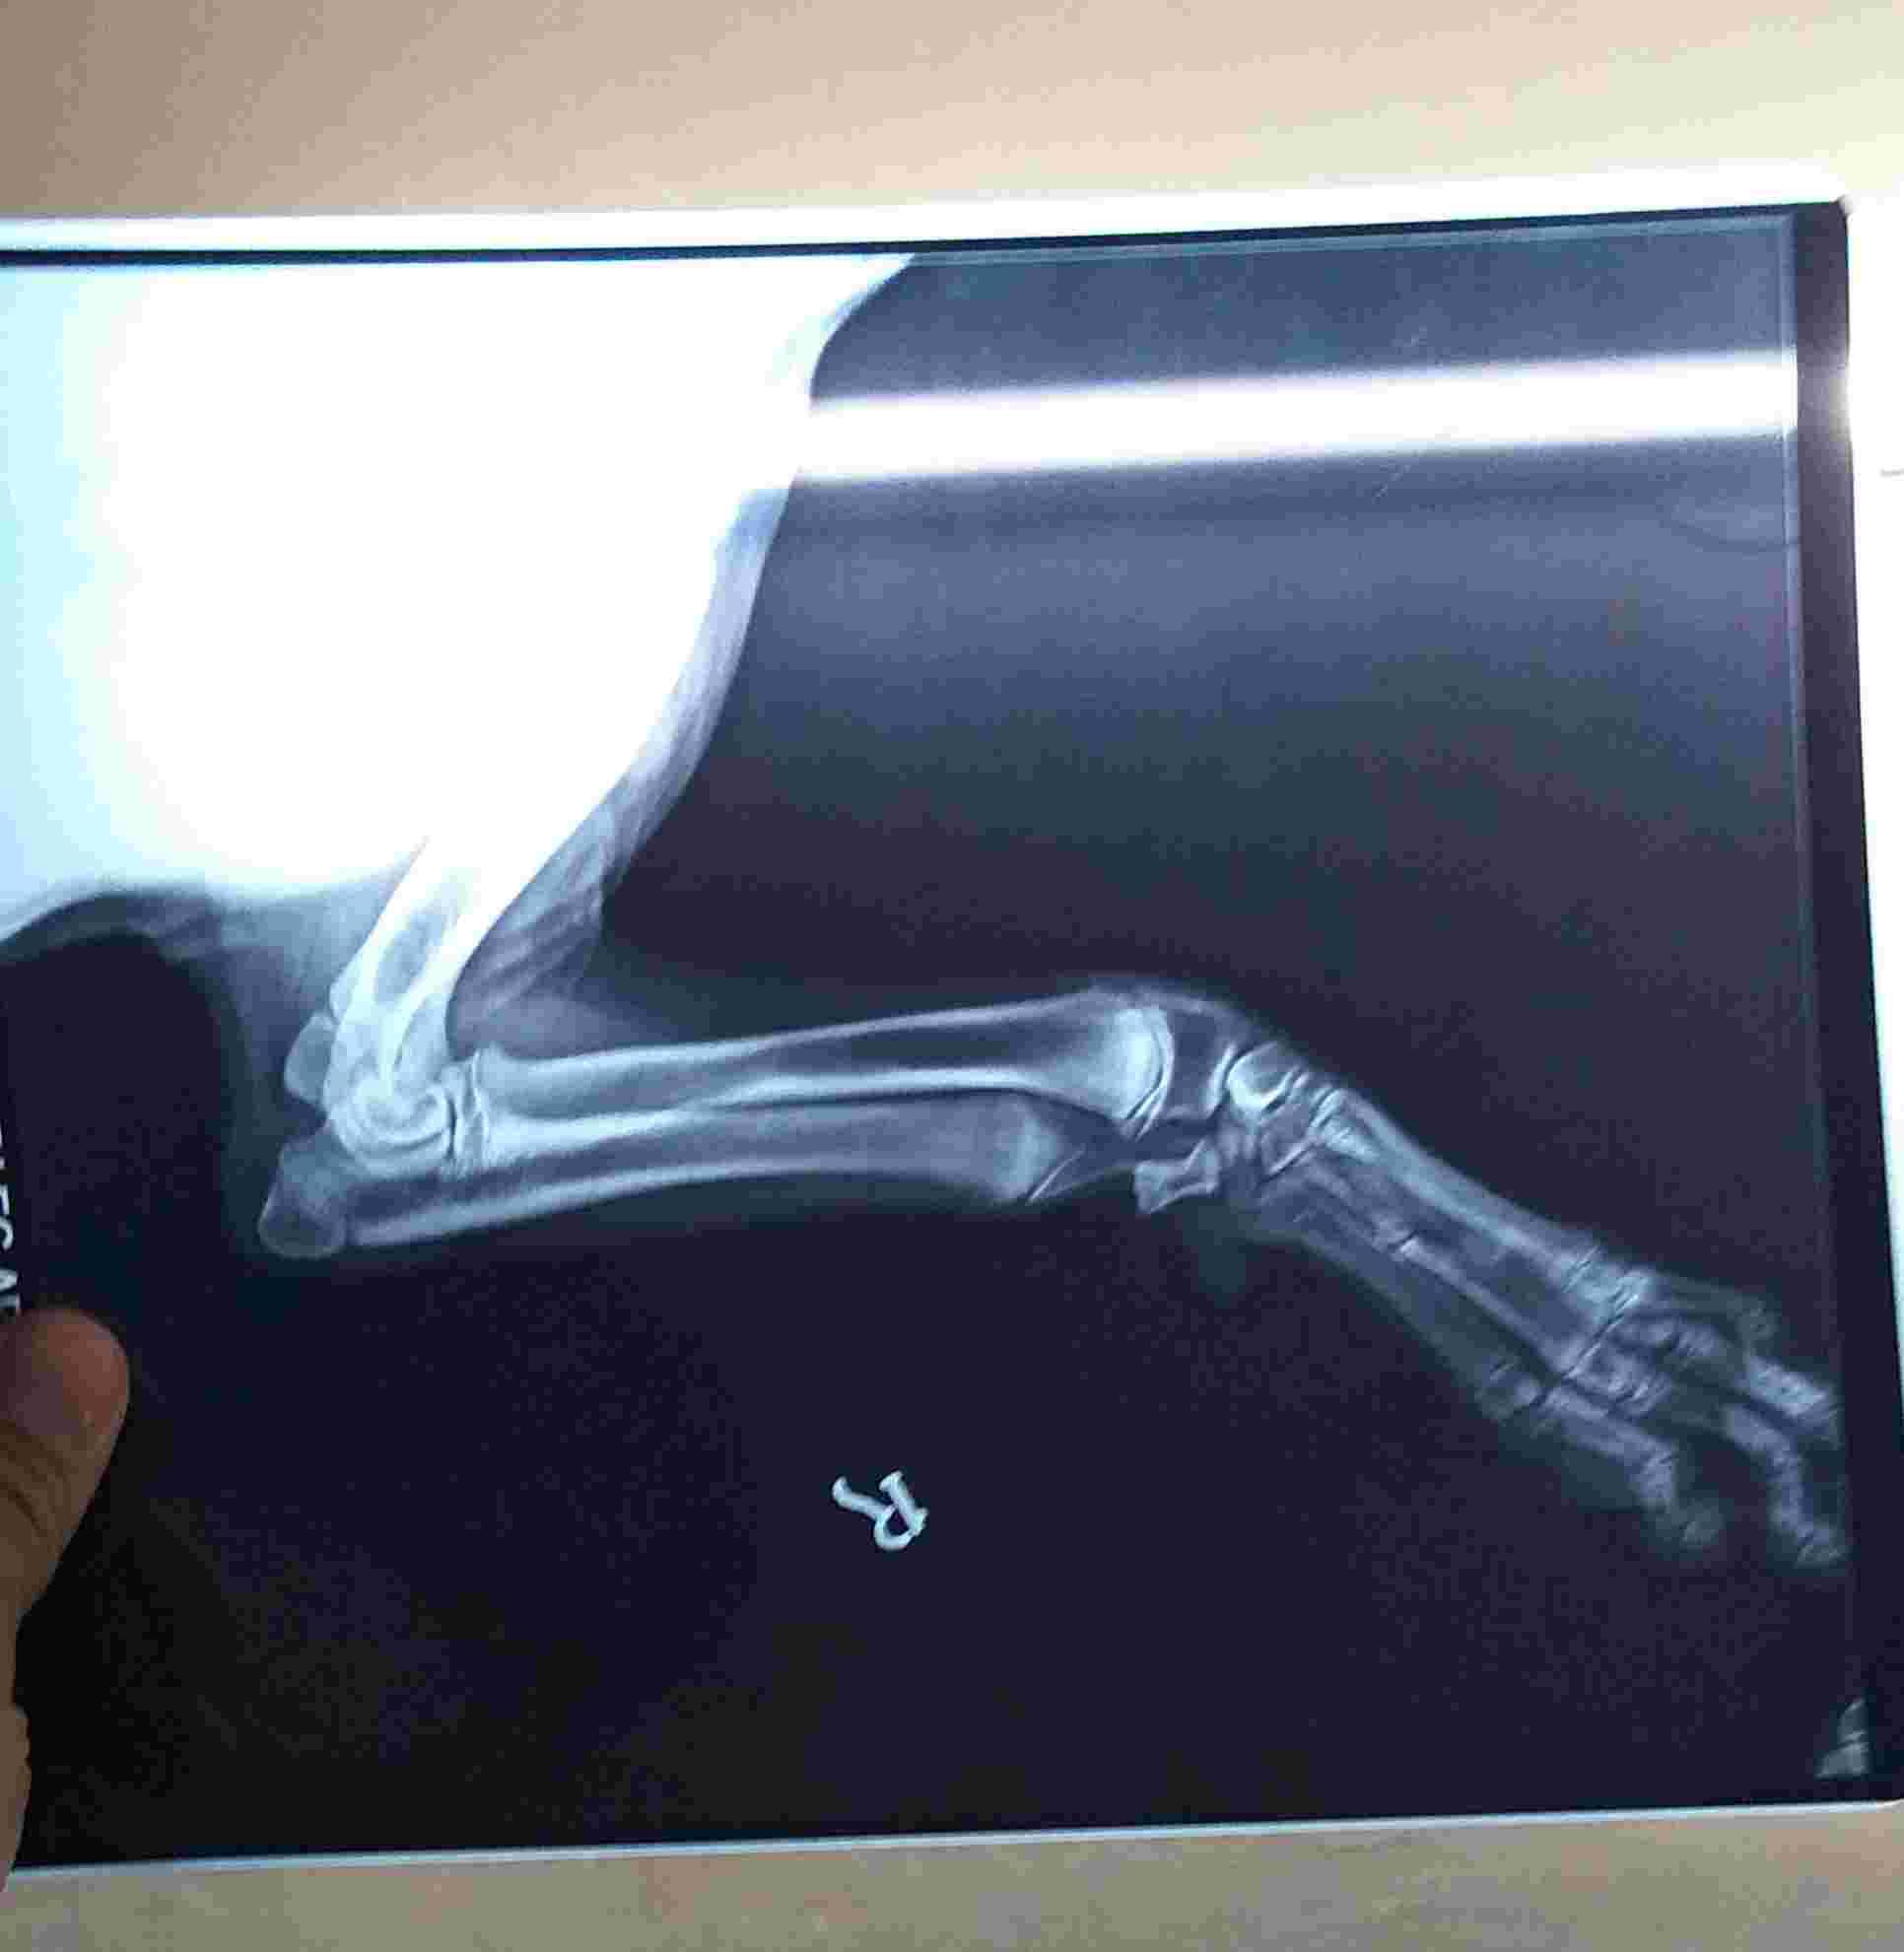

My dog has carpal valgus. Will he get arthritis or joint issues?

Like by looking attach xray report you said he has carpal valgas deformity so will his life span going to affect ? Will he going to have arthritis or any other problem related to this carpal valgas deformity later in life or in coming days ?

At his age, Danny is likely done growing. Having a valgas deformity will predispose him to developing arthritis or other joint issues later in life, but should not affect his lifespan. There are treatment options you can discuss with your veterinarian or a veterinary orthopedic specialist.